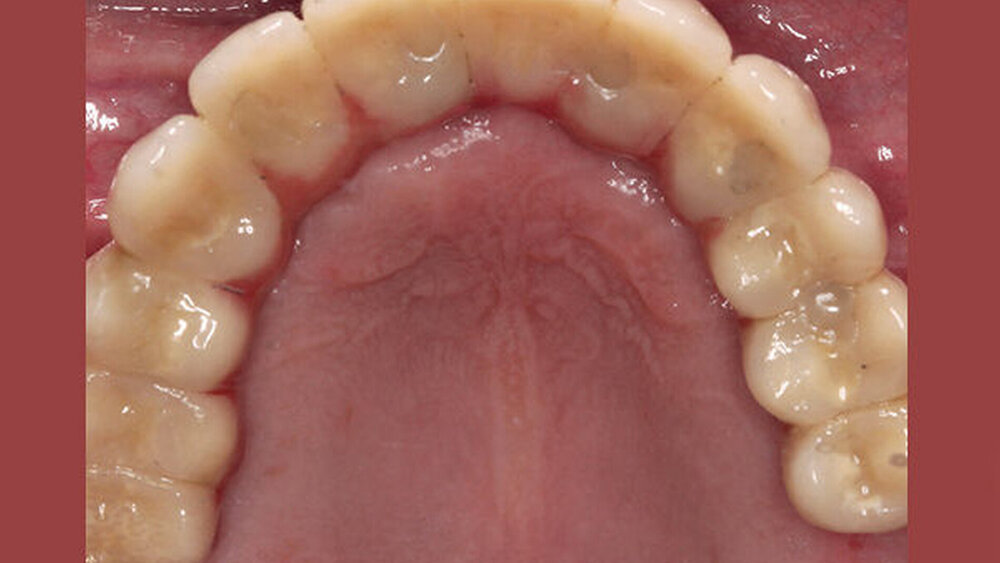

Das ist ein All-on-four- bzw. -six-Konzept für die Sofortversorgung zahnloser Kiefer, korrekt?

Buhtz: Korrekt, die Voraussetzung ist lediglich die Generierung von DICOM- und STL-Daten, die im Computer exakt übereinandergelegt werden können. Dann erfolgen die Behandlungsplanung wie gewohnt mit ICX-Magellan und die provisorische ‧Versorgung mit dem präfabizierten, chairside hergestellten verklebten PMMA-Provisorium (ICX-‧Smile‧bridge). Seit eineinhalb Jahren arbeiten wir zudem mit dem medentis Fräszentrum Denta5 zusammen.

Buhtz: Wir schicken die Scan-Daten, ein Wax-up und ggf. das Modell mit den Laborimplantaten an das medentis-Fräszentrum und erhalten zwei Tage später die verschraubte Unterkonstruktion. Denta 5 gibt es bereits seit einigen Jahren. Doch erst seit wir einen eigenen Modellscanner haben, stellen wir verschraubte Brücken auf diese Weise her. Jetzt habe ich eine Zahntechnikerin, die damit gut klarkommt. Full-arch-Versorgungen sind bei uns allerdings nicht das Tagesgeschäft, wir machen das vielleicht zehn- bis zwanzigmal pro Jahr. Unsere Patientenklientel ist in der Regel nicht zahnlos.

Die ideal prothetisch ausgerichtete Implantatposition ist der wohl wichtigste Erfolgsfaktor in der Implantologie. Mit ICX-Magellan lässt sich das einfach, schnell und kostengünstig realisieren.